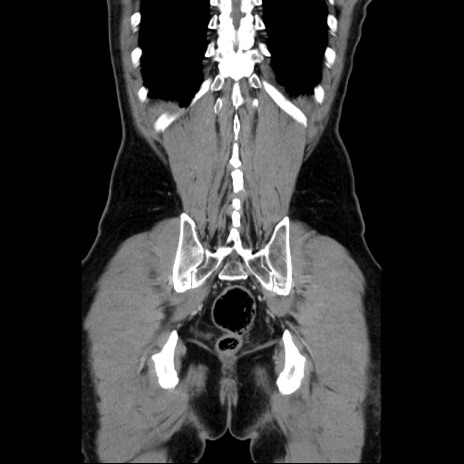

症例34(冠状断像)

【症例】60歳代 男性

【主訴】右鼠径部膨隆

【現病歴】1年程前より右鼠径部膨隆あり。自己にて還納可能だったため放置していた。3時間前より右鼠径部の脱出を認め、還納困難となり受診。

【既往歴】高血圧

【身体所見】右鼠径部に小児頭大の膨隆あり。弾性硬であり、用手還納は困難。左鼠径部にも膨隆を認める。脱出はなし。

【データ】WBC 15500、CRP 測定なし